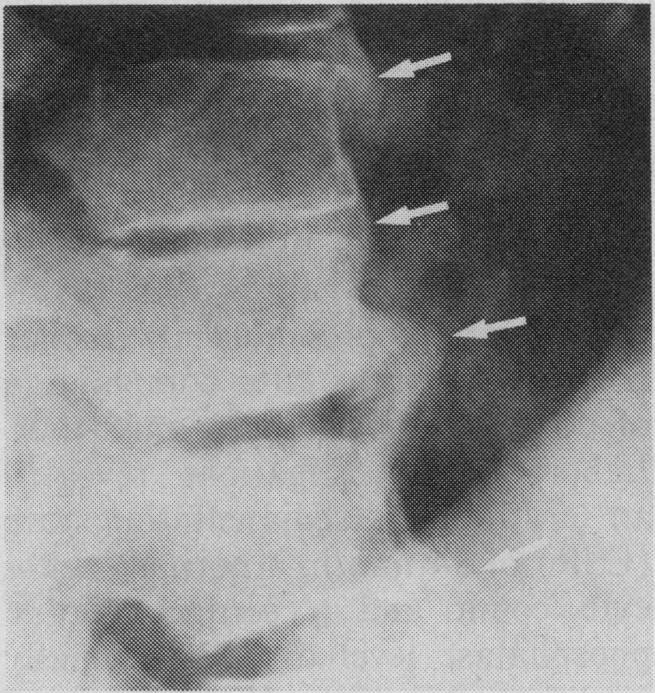

Vertebral osteomyelitis represents a diagnostic challenge to the clinician. Two cases of pyogenic vertebral osteomyelitis occurring weeks to months after a urinary tract infection with Escherichia coli are described. The rarity and subtle clinical presentation of this condition, the presence of pre-existing degenerative arthritic changes, and delayed appearance of radiologic signs of progression to destructive osteomyelitis contributed to a significant delay in diagnosis. Increased awareness of vertebral osteomyelitis as a clinical entity combined with information from radionuclide scanning may permit earlier detection of this condition.

脊椎骨髓炎对临床医生来说是一项诊断挑战。本文描述了两例在大肠杆菌引起的尿路感染数周或数月后发生的化脓性脊椎骨髓炎病例。这种疾病的罕见性和微妙的临床表现、先前存在的退行性关节炎改变以及进展为破坏性骨髓炎的放射学征象出现延迟,导致诊断出现显著延迟。提高对脊椎骨髓炎作为一种临床实体的认识,并结合放射性核素扫描的信息,可能有助于更早地发现这种疾病。